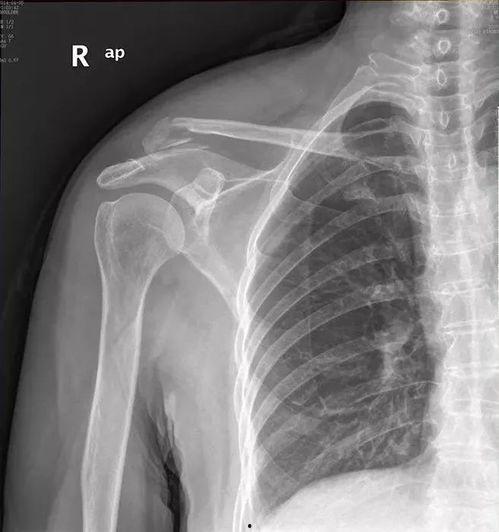

• 肩锁关节脱位图片,图解与概述

最近有个朋友不小心摔了一跤,结果肩锁关节脱位了。这可真是让人心疼啊!肩锁关节脱位,听起来是不是有点陌生?别急,今天我就带你来详细了解一番,让你对这个神秘的关节有个清晰的认识。而且,我还准备了一些肩锁关节脱位的真实图片,让你直观地感受一下这个问题的严重性。肩...